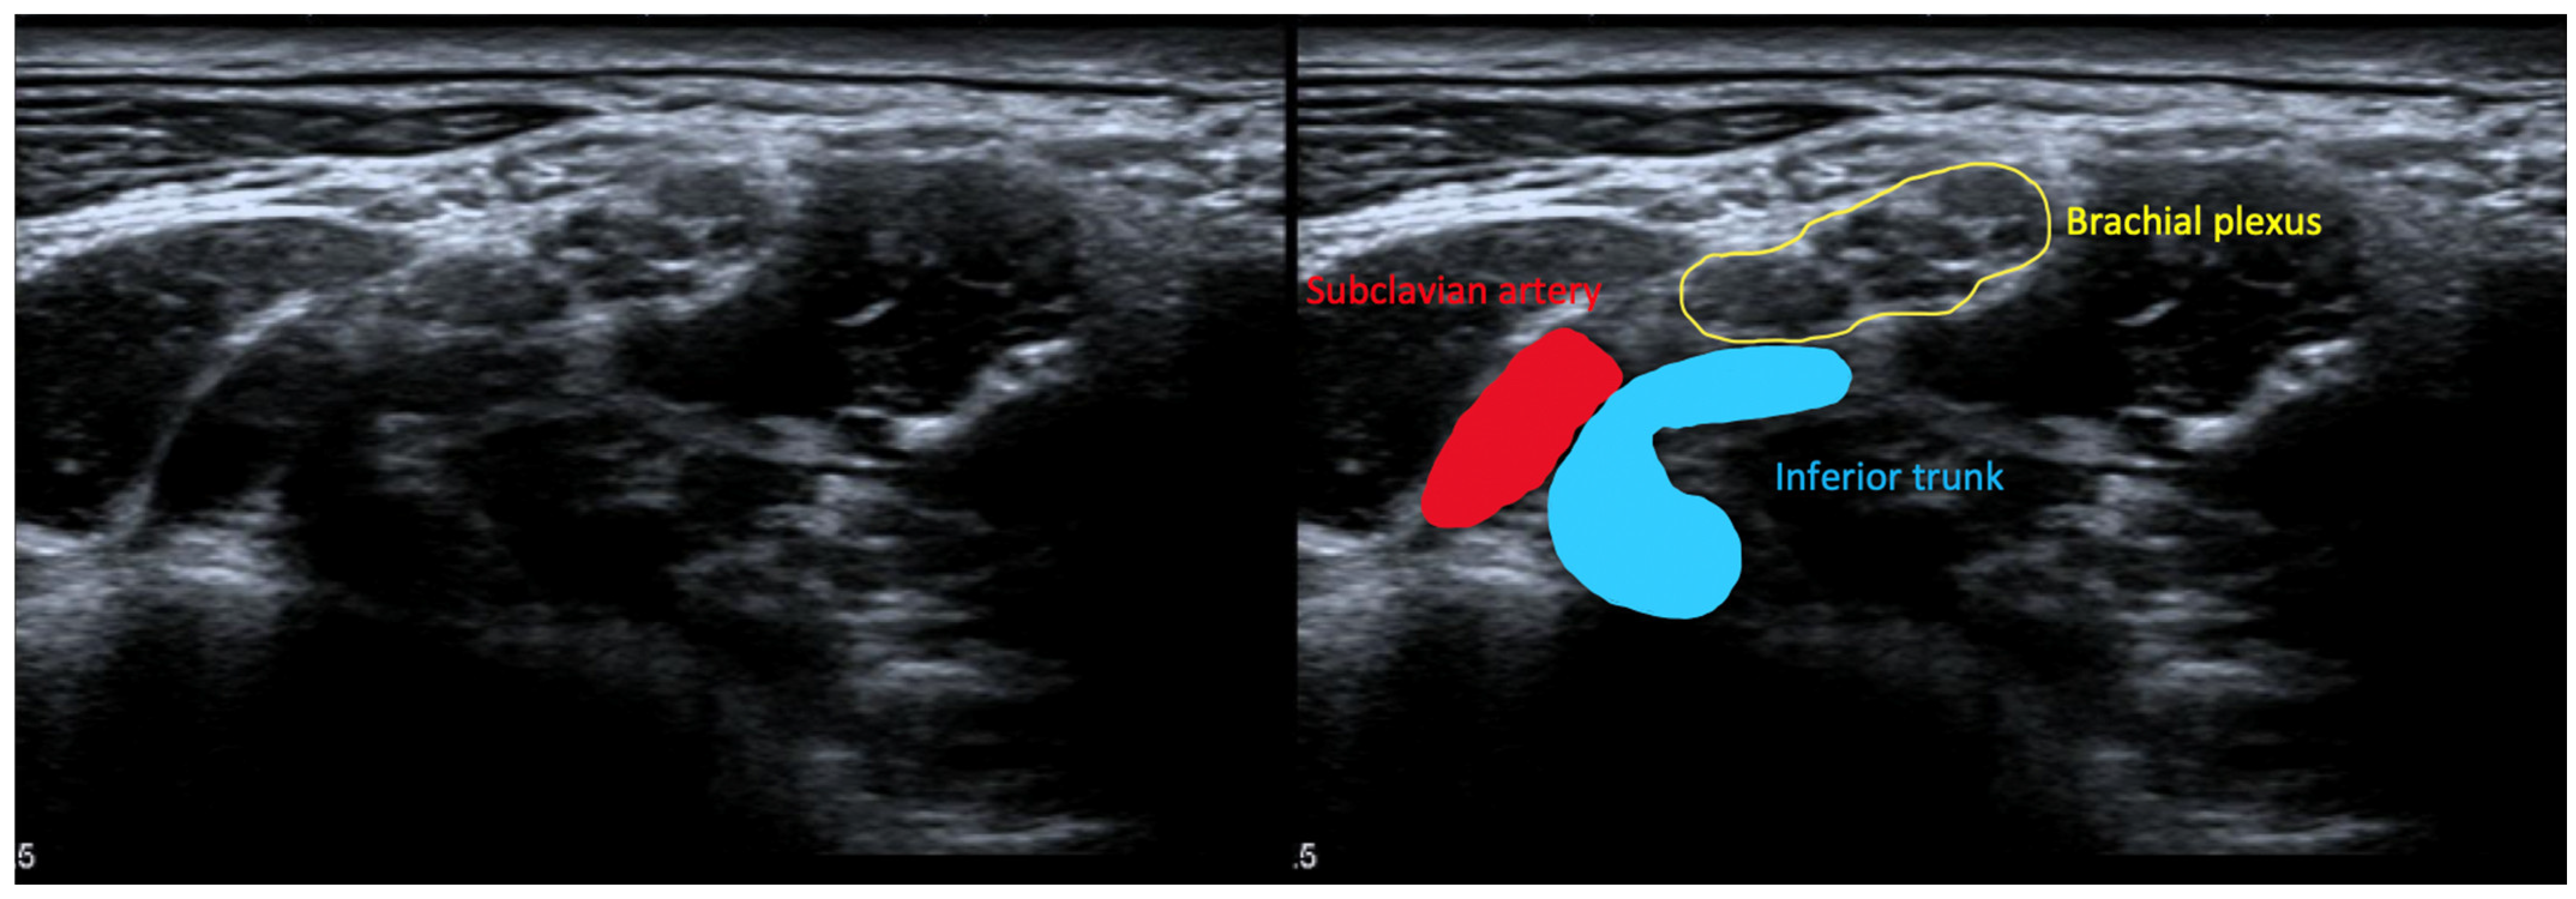

6.3.4. High-Resolution Ultrasound for NTOS

- Dollinger, P.; Böhm, J.; Arányi, Z. Combined nerve and vascular ultrasound in thoracic outlet syndrome: A sensitive method in identifying the site of neurovascular compression. PLoS ONE 2022, 17, e0268842. [Google Scholar] [CrossRef] [PubMed]

- Arányi, Z.; Csillik, A.; Böhm, J.; Schelle, T. Ultrasonographic Identification of Fibromuscular Bands Associated with Neurogenic Thoracic Outlet Syndrome: The “Wedge-Sickle” Sign. Ultrasound Med. Biol. 2016, 42, 2357–2366. [Google Scholar] [CrossRef]

- Pesser, N.; Teijink, J.A.W.; Vervaart, K.; Goeteyn, J.; Gons, R.A.R.; van Sambeek, M.R.H.M.; van Nuenen, B.F.L. Value of Ultrasound in the Diagnosis of Neurogenic Thoracic Outlet Syndrome. Eur. J. Vasc. Endovasc. Surg. 2020, 59, 852–853. [Google Scholar] [CrossRef] [PubMed]